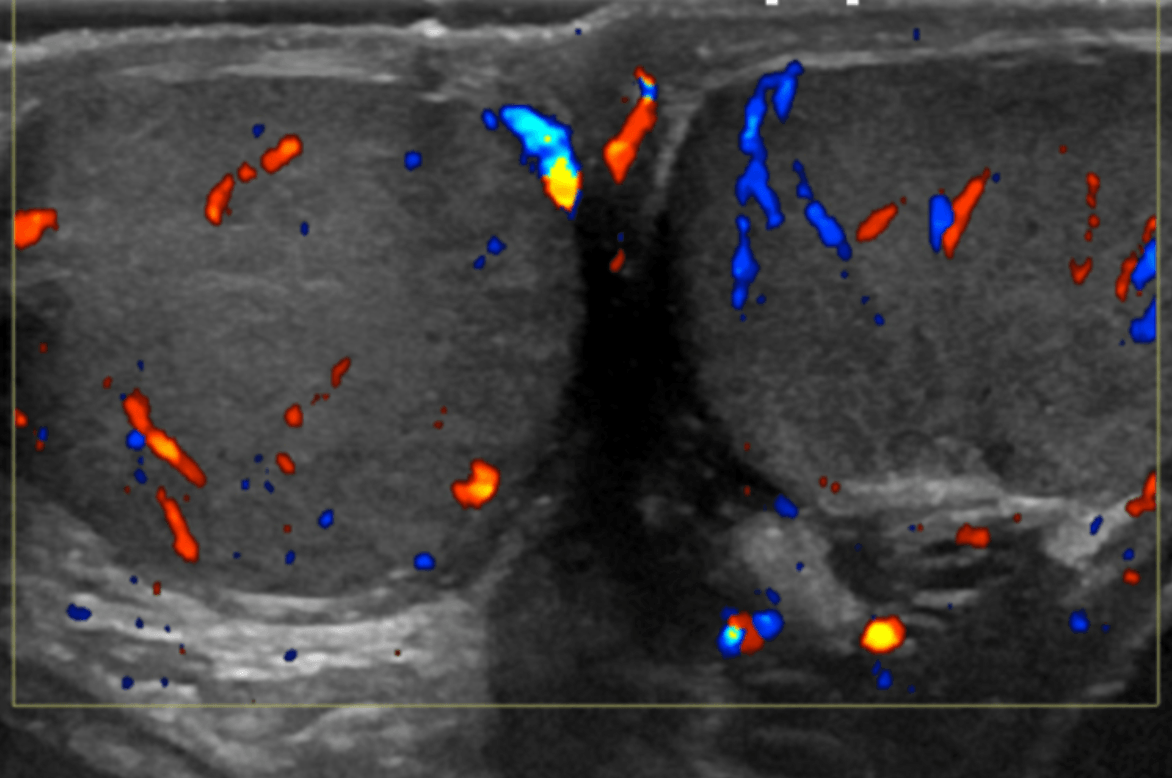

Thyroid 20 minutes

Whole body ultrasounds provide a non-invasive, painless, imaging option, allowing for the assessment of various organs without exposure to radiation.

This screening can help identify abnormalities such as tumors, cysts, or vascular issues at an early stage, potentially improving treatment outcomes. Our general screening exams include: breast, thyroid, kidneys, liver, spleen, aorta, pancreas, and calf veins.